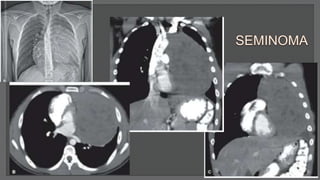

Less than half of all malignant primary mediastinal germ cell tumor

Occur in young adult males who are 20 to 40 years of age

Typically slow growing, quite large before the symptoms (chest pain, dyspnea, cough)

Chest CT: a bulky, lobulated, but homogeneous mass with only occasional invasion of

adjacent structures

60%-70% of patients will have metastatic disease at the time of diagnosis, most

commonly to bone, lungs, liver, spleen, or brain

Tumor markers: β-hCG levels are mildly elevated (<100 ng/mL)